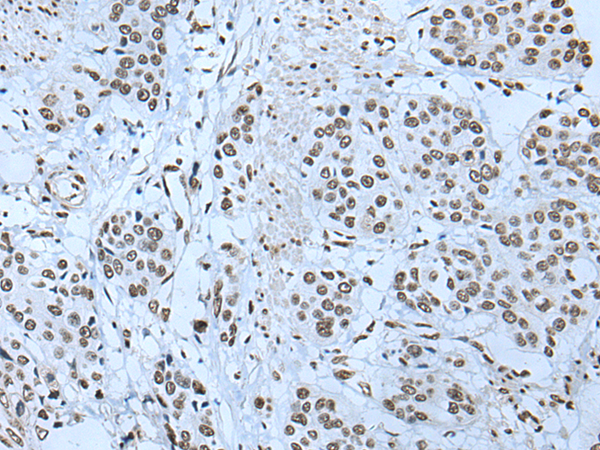

分类: 科研抗体货号: P12818别名: ATG1; ATG1A; UNC51; hATG1; Unc51.1应用: IHC反应种属: Human